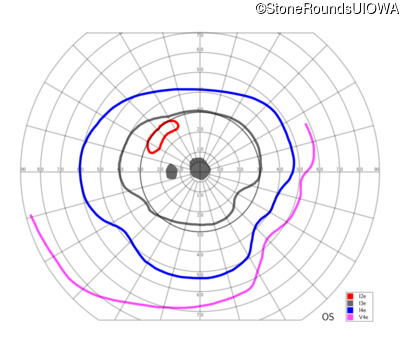

This 52 year old man had normal vision until his mid 30's when he began to have trouble distinguishing colors. the issuing 10 years he had a gradual loss of visual acuity accompanied by increasing photophobia.

| Age at visit: 55 years |

| Age at visit: 58 years |

| Age at visit: 61 years |

| Age at visit: 64 years |

| XL Cone and Cone Rod Dystrophy | RPGR | Gly1093 del2gGA | XL |